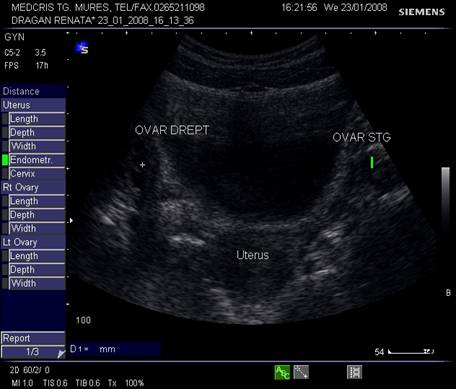

Ovarele. Sectiunea longitudinala directa, spre peretele lateral pelvin, la ecografia transvaginala, pune in evidenta ovarele cu forma elipsoidala. Acestea au structura ecografica relativ slab ecogena, in apropierea si sub vasele iliace.[5]

Marimea ovarelor: inainte de menopauza aproximativ 3,5 x 2,5 x 1,5 cm si aproximativ 2,0 x 1,5 x 1 cm dupa menopauza. Nu se poate aprecia volumul ovarian decat masurand cele trei diametre in planuri sagitale, oblice si coronale ale pelvisului.[1,2,9]